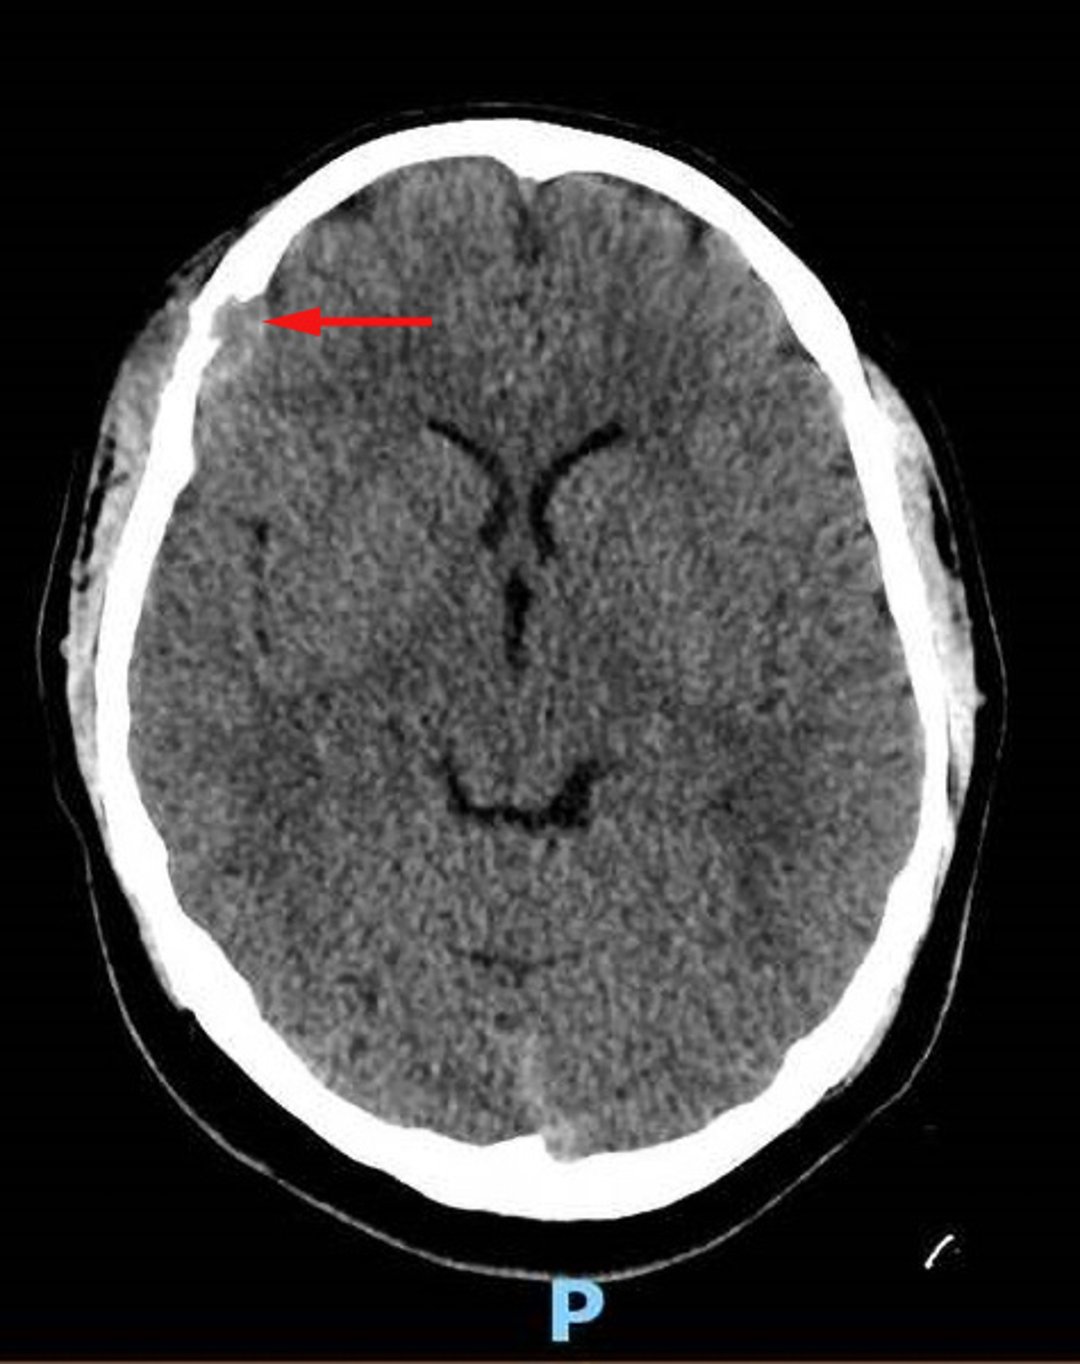

頭蓋のMRIまたはCT(側頭骨病変を検索するため)

眼窩のMRIまたはCT(顔面骨病変を検索するため)

頬骨弓,蝶形骨,眼窩,篩骨,または側頭骨の病変は,中枢神経系リスク病変に分類され,頭蓋および顔面における神経変性疾患のリスクが高い。